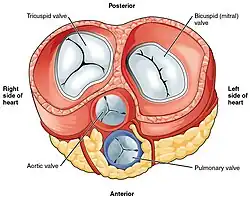

Сердце птиц и млекопитающих (зверей) — четырёхкамерное. Различают: правое предсердие, правый желудочек, левое предсердие и левый желудочек. Кровообращение: из одной или двух передних (верхних) и задней (нижней) полых вен кровь поступает в правое предсердие, затем в правый желудочек, затем по малому кругу кровообращения кровь проходит через лёгкие, где обогащается кислородом (оксигенируется), поступает в левое предсердие, затем в левый желудочек и, далее, в основную артерию организма — аорту (птицы имеют правую дугу аорты, млекопитающие — левую). Большой и малый круги кровообращения полностью разобщены.

Между предсердиями и желудочками находятся фиброзно-мышечные клапаны — справа трёхстворчатый (или трикуспидальный), слева двустворчатый (или митральный). На выходе из желудочков соединительнотканные клапаны (лёгочный справа и аортальный слева). Клапаны открываются только в сторону желудочков и поэтому пропускают кровь только в одном направлении: из предсердий в желудочки. Открываться в сторону предсердий створкам клапанов мешают сухожильные нити, отходящие от поверхности и краёв клапанов и прикрепляющиеся к мышечным выступам желудочков. Мышечные выступы, сокращаясь вместе с желудочками, натягивают сухожильные нити, чем препятствуют выворачиванию створок клапанов в сторону предсердий и обратному оттоку крови в предсердия.